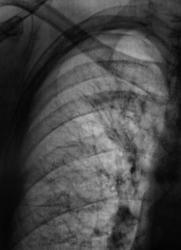

После расшифровки цифровых флюорограмм, пациент взят на контроль, дообследован. Ваше мнение уважаемые коллеги?

Можно предположить гиповентиляцию S2. Необходима КТ.

А если нет возможности сделать КТ, выполнить линейную томографию на в/долевой и сегментарные бронхи в/доли справа, бронхоскопию... В связи с этим у меня вопрос: Валентин Львович, я знаю у вас очень много случаев туберкулеза, но почему ваши лаборанты практически никогда не делают сразу срезы на бронхиальное дерево?

А где предыдущие данные, или это "с хутора"? Тогда КТ надо или бронхоскопию, если терять нечего - динамика покажет.

Вот посему, мы и предположили, наличие, как ранее называли, перибронхиального рака. Правда сейчас, он по всей видимости, отнесен к одному из видов БАР.

а по каким признакам здесь заподозрен БАР? Я почему то был уверен что это туберкулёз?

Туберкулез, в данном случае, нельзя исключить из дифряда, но он явно не первый.